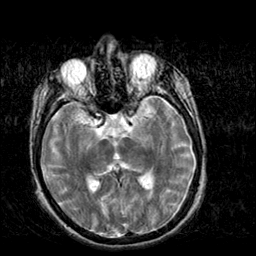

Creutzfeld-Jakob disease: T2-weighted MR -- Slice #10

[Home][Help][Clinical] Slice 10